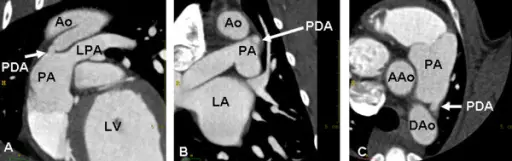

Patent Ductus Arteriosus (PDA)

A patent ductus arteriosus (PDA) results from failure of the ductus arteriosus close.

Patent ductus arteriosus (PDA) is linked to congenital rubella.

Patent ductus arteriosus (PDA) results in a left-to-right shunt between the pulmonary artery and the aorta.

The ductus arteriosus generally diverts blood away from the lungs and toward the aorta during development.

Patent ductus arteriosus (PDA) is typically asymptomatic at birth with a holosystolic ‘machine-like’ murmur.

Patent ductus arteriosus (PDA) may result in lower extremity cyanosis and Eisenmenger syndrome.

Treatment of patent ductus arteriosus (PDA) involves indomethacin, which decreases prostaglandin E1 (PGE1), resulting in PDA closure.

Note that PGE1 maintains patency of the ductus arteriosus.